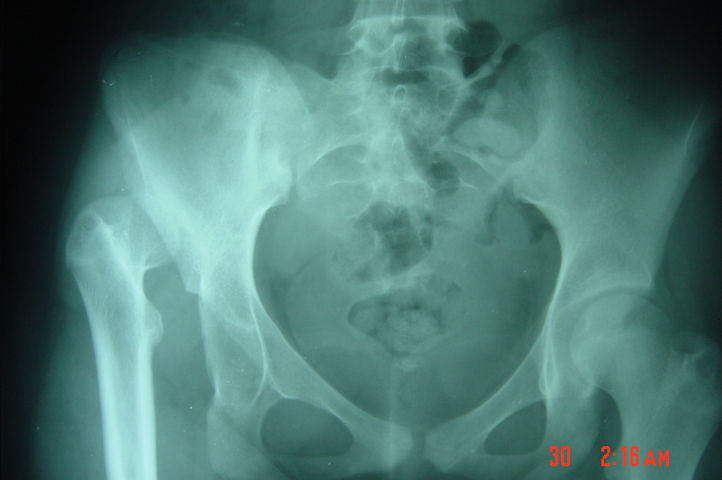

According to general belief if the diagnosis of developmental dysplasia of the hip ( DDH - former congenital dislocation hip or dysplasia hip -dysplasia hip baby) is delayed, the soft tissue and bony adaptive changes will be well-established and it is necessary to perform an open reduction of the hip often with surgical correction of the shape of the acetabulum and femur by osteotomy. This adds considerably to the scope of the intervention and it is often not possible in these cases to create a normal hip. If a concentric stable and well contained hip cannot be established by the age of four, the prospect of residual dysplasia and disability is almost universal. However, despite a deceptive good function during childhood, the abnormal hip shape would lead to altered mechanics and in adolescence fatigue pain and limp may develop, which progressively will lead to premature osteoarthritis of the hip at an early age , necessitating joint replacement surgery (total hip arthroplasty).